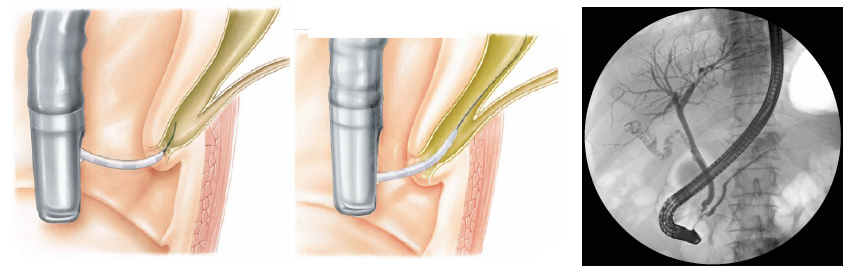

Com o paciente sedado, o aparelho é introduzido pela boca e passa através do esôfago e do estômago para o duodeno, local onde fica posicionada a papila duodenal.

Para o exame, o médico utiliza um tubo flexível e iluminado chamado duodenoscópio, que possui uma câmera na lateral do aparelho, diferente do endoscópico padrão que possui a câmera na frente do aparelho.

Durante o exame o médico passa de um pequeno cateter (tubo) dentro do ducto biliar comum e injeta um contraste que pode ser visto com um exame de raio-X. A via biliar e eventualmente o pâncreas podem então ser examinados para anormalidades.

Com o paciente sedado, o aparelho é introduzido pela boca e passa através do esôfago e do estômago para o duodeno, local onde fica posicionada a papila duodenal.

Para o exame, o médico utiliza um tubo flexível e iluminado chamado duodenoscópio, que possui uma câmera na lateral do aparelho, diferente do endoscópico padrão que possui a câmera na frente do aparelho.

Durante o exame o médico passa de um pequeno cateter (tubo) dentro do ducto biliar comum e injeta um contraste que pode ser visto com um exame de raio-X. A via biliar e eventualmente o pâncreas podem então ser examinados para anormalidades.

O procedimento pode ser feito em clínica ou hospital. Será dado um sedativo para você relaxar. A parte de trás de sua garganta será borrifada com um anestésico local para evitar engasgos no endoscópio. Seu médico irá inserir o duodenoscópio em sua boca através de seu esôfago, estômago e duodeno até atingir o ponto em que o ducto biliar comum abre para o intestino (papila duodenal). Seu médico irá passar um pequeno cateter (tubo) através do aparelho e o introduzirá, pelo orifício da papila, no ducto a ser estudado. Por este cateter o médico injetará contraste nos ductos para que eles apareçam de maneira clara aos raios X. Os raios X são tirados logo após o contraste ser injetado. Se o exame mostrar pedras, o seu médico pode usar uma ferramenta para quebrá-las e movê-los para o intestino. O seu médico pode também aumentar a abertura da papila duodenal, para permitir que as pedras passem para o intestino mais facilmente. Amostras de tecido podem ser tomadas para testes em laboratório de anatomia patológica se seu médico achar necessário.